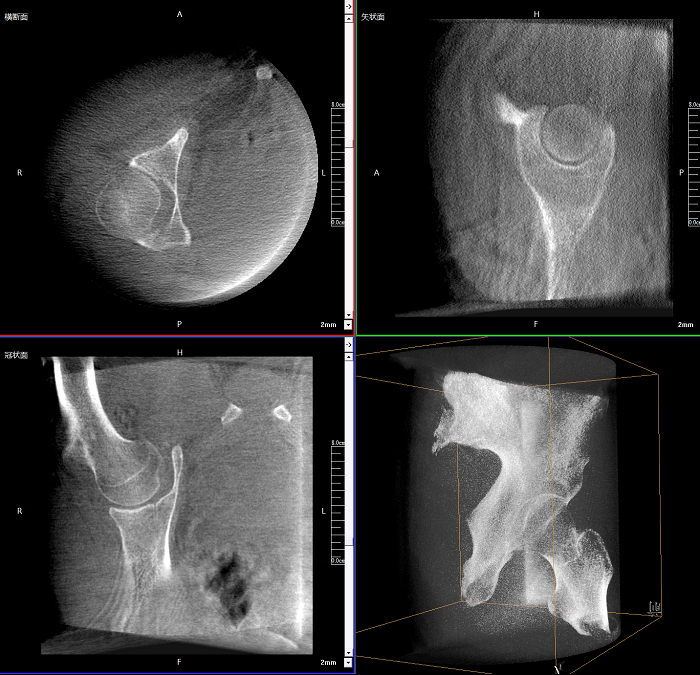

術(shù)中實(shí)時(shí)生成橫斷面、矢狀面、冠狀面及三維影像,可在任意切面、任意角度評估植入物和解剖結(jié)構(gòu)的相對位置。

術(shù)中CT檢查 減少翻修概率

通過術(shù)中三維影像的檢查,可以立即發(fā)現(xiàn)植入物的錯(cuò)位,減少不必要的第二次手術(shù),減少并發(fā)癥概率以及感染風(fēng)險(xiǎn)。

Clinical picture

臨床圖片